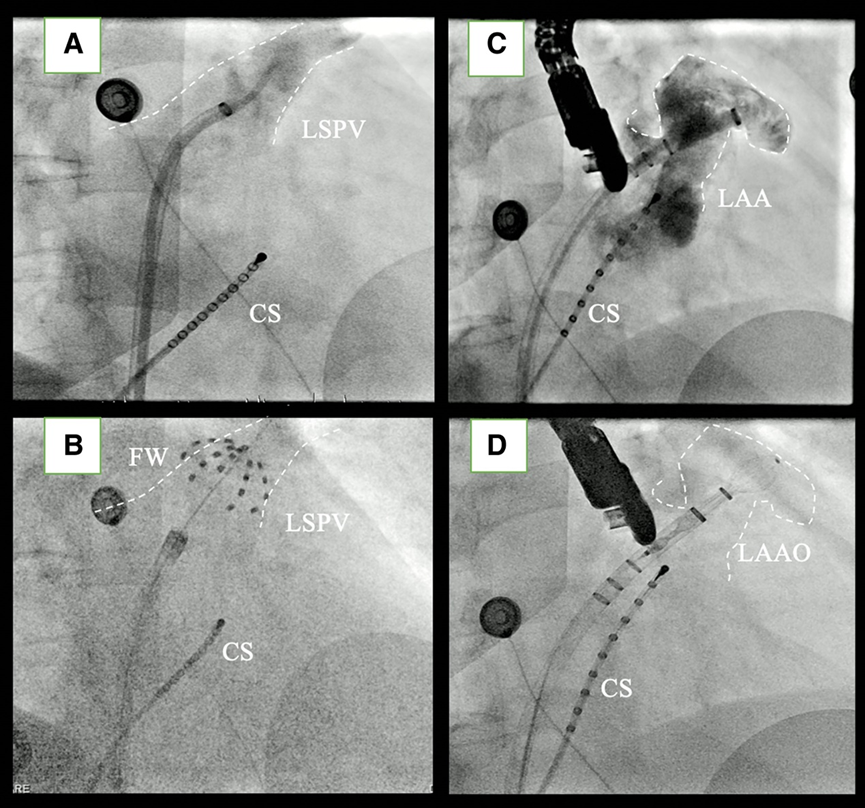

将诊断导管(6-F,Inquiry,雅培)置于冠状窦中。在DSA引导下进行了单次房间隔穿刺(SL1,8.5-F,雅培)。肺静脉造影后,选择了31mm PFA消融导管(Farawave®,Farapulse Inc.,美国)。左上肺静脉 (LSPV) 中通过导丝将房间隔鞘与13-F可调弯输送鞘 (Faradrive®,Farapulse Inc.,美国) 交换。每个肺静脉采用 10次消融方案进行消融 (4次Flower和4次Basket形态+2次Olive橄榄形额外消融)。“Olive橄榄形”是直径减小的Basket形态,用于消融肺静脉口相对较深的位置。采用这种增加2次额外消融的方案旨在提高肺静脉隔离的持久性。

最后一次消融后,通过电复律恢复窦性心律。PV 传入阻滞通过PFA消融导管Olive橄榄型在肺静脉口部起搏确认。然后插入经食道超声心动图 (TEE) 探头来引导左心耳封堵术。有趣的是,观察到LSPV和LAA之间的嵴部肿胀,但是水肿似乎不涉及着陆区的水肿,因此我们继续进行左心耳封堵术手术。

在LSPV中,将 Faradrive® 鞘管通过导丝置换成 Boston Scientific双向可调弯 14Fr 输送鞘管。使用 6 Fr猪尾巴导管将WATCHMAN14Fr 输送鞘管引导至 LAA,并在RAO30°、CRA15° 和CAU20° 角度下进行造影。造影或 TEE 上的 LAA 着陆区最大直径为 22.8 mm(图1),因此选择了WATCHMAN FLX™ 27 mm封堵器。该封堵器在LAA中推送(图 2),并且可以在第一次尝试时成功植入,而无需重新定位。在多普勒序列中,没有观察到残留漏。患者出院时接受了双重治疗,即每日两次服用150mg达比加群作为直接口服抗凝剂 (DOAC) + 阿司匹林,并计划在手术后 6 周进行TEE随访。有趣的是,TEE 显示嵴部部水肿完全消退,封堵器近端轻微移动。压缩保持22mm,封堵令人满意,因此DOAC治疗(每日两次服用150mg达比加群)中断,继续服用阿司匹林。在 6个月的随访期间,未记录到中风或出血,也未记录到复发的房颤。

图表2( A ) RAO左上肺静脉造影透视图像 ( B ) 使用 31 mm 脉冲场消融导管 (Farawave®) 在RAO 30° 左上肺静脉中进行肺静脉隔离的透视图像。( C ) RAO向 30°CAR15° 的左心耳造影的透视图像。( D ) 使用 27 mm WATCHMAN FLX™ 在RAO 30°CRA15° 进行的左心耳封堵的透视图像。可以看到 LAA-PV嵴部的术中水肿。在所有图像中都可以看到位于冠状窦中的CS导管。